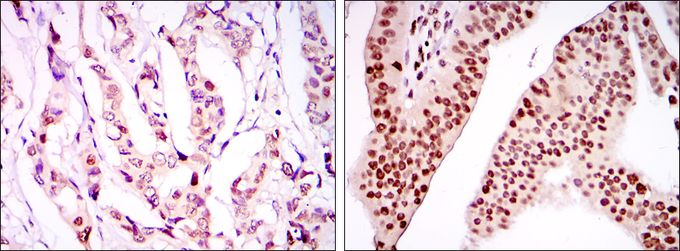

IHC-P analysis of lung cancer tissue (left) and brain tissue (right) using GTX80396 PSIP1 antibody [6E4].